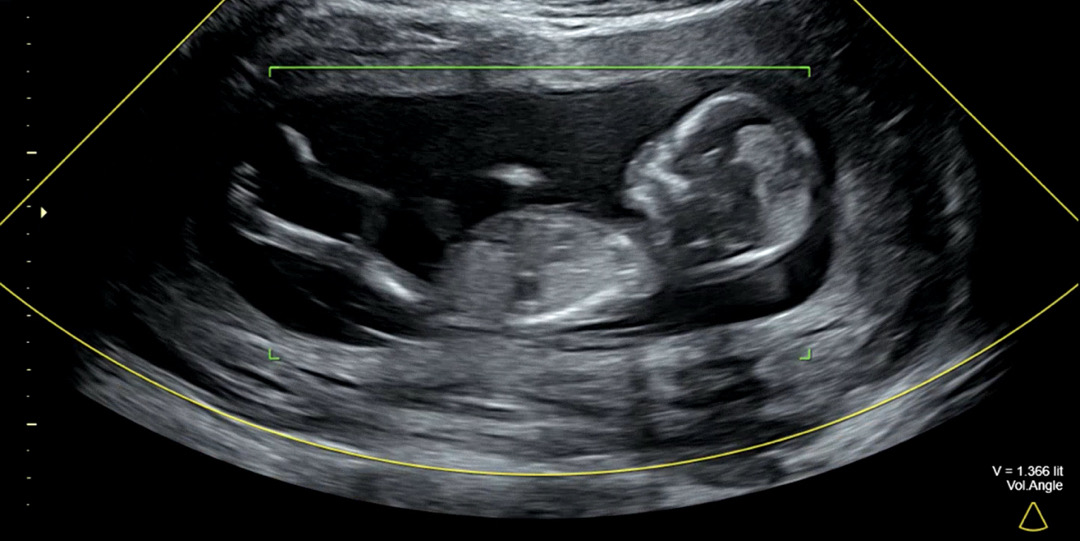

남매맘확정! 13주 아기 다리가 늘씬해요

13주 2일 초음파 사진이에요ㅎㅎ 왠지 실루엣이 딸같다 했는데 니프티결과 진짜로 공주님 당첨이네요! 그니저나 첫째때는 이렇게 쭉 뻗은 다리를 본적이 없는 것 같은데..! 왠지 모델같은 아기가 태어나려나? 하고 벌써부터 도치맘이에요ㅋㅋㅋㅋ 아가 얼른 만나쟈